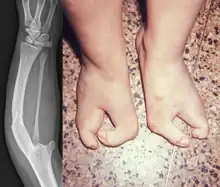

Van Den Berghe Dequeker syndrome, also known as ulnar hypoplasia-split foot syndrome is a very rare congenital limb malformation syndrome which is characterized by severe ulnar hypoplasia, absence of the index to pinky finger in both hands, and split-foot.[3]

It was first discovered in 1978 by H van de Berghe et al., when they described four males (consisting of three brothers and one maternal nephew) of a two-generation family with a "lobster-claw foot" and an "ulnar defect".[3] The lobster-claw architecture of the foot is described as the I and V toes being the only ones developed, resulting in the appearance of a split-foot. Morphology of the ulnar defect ranged from a shortened ulna to complete absence of the ulna with a curved, thickened radius. Van de Berghe et al. also noticed that some female members (the mother and maternal aunt of an affected male) showed minor hypoplasia and slight deformations of the toes, as well as shorter ulnas and marginally curved radii. At the time of discovery, ulnar aplasia occurred sporadically and infrequently, therefore, the documentation of this occurring familially was considered to be rare.[3]